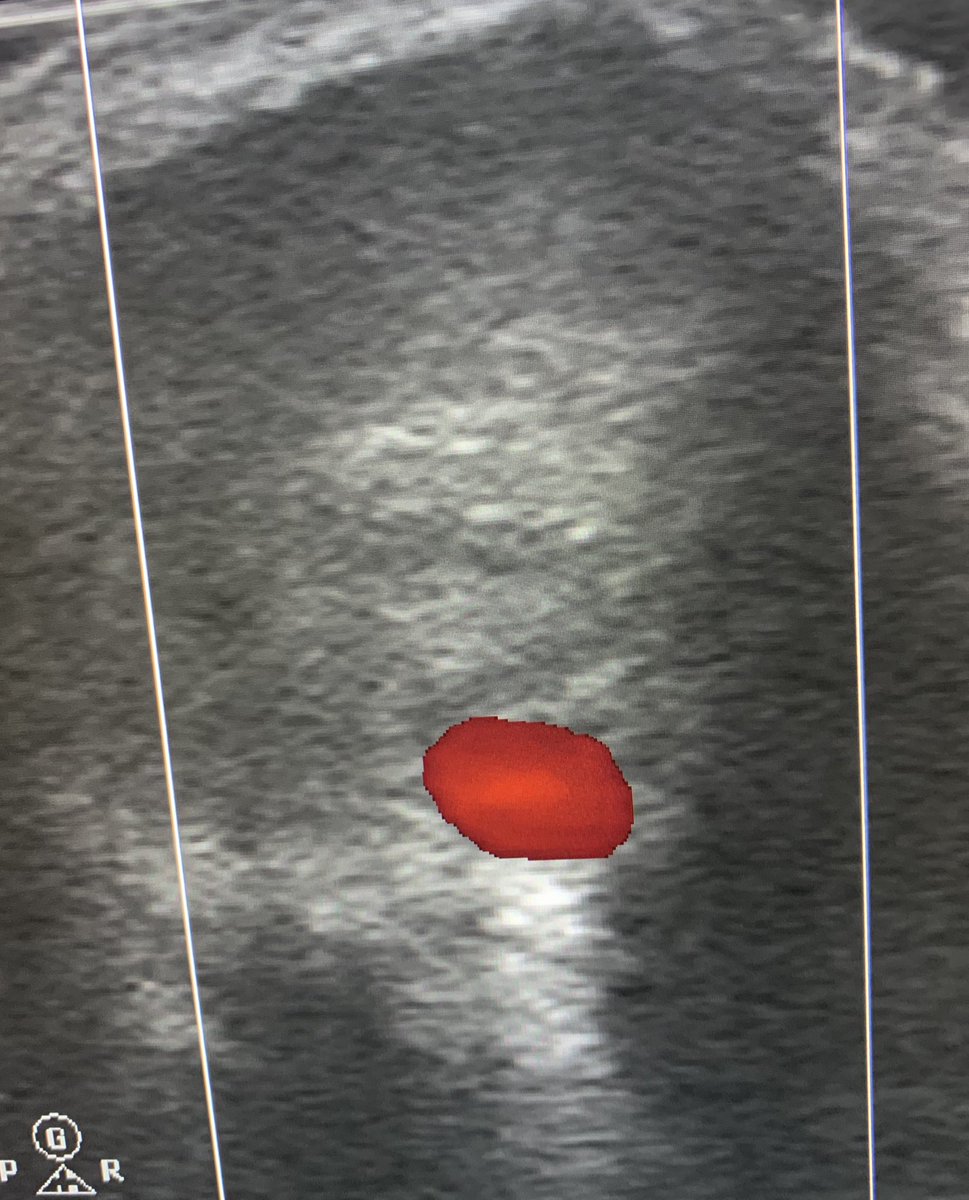

Day 5 @NHSHarlow. Our #irad team perform CT guided spinal injections for pain management. Service is popular with our patients & supported by our spinal surgeons. Photos 1)cervical interlaminer epidural 2) thoracic transforaminal 3) SIJ 4) cervical transforaminal. Zaid A H Aldin

Day 5 @NHSHarlow. Our #irad team perform CT guided spinal injections for pain management. Service is popular with our patients &amp; supported by our spinal surgeons. Photos 1)cervical interlaminer epidural 2) thoracic transforaminal 3) SIJ 4) cervical transforaminal. <a href="/ZaidAHAldin1/">Zaid A H Aldin</a>